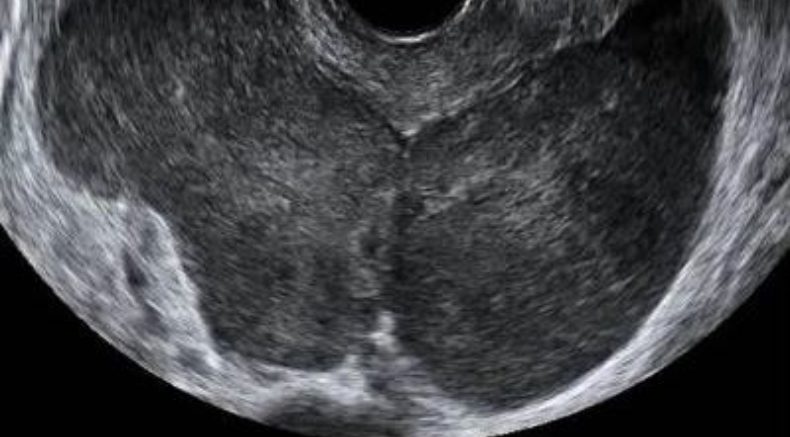

At ultrasound examination metastatic tumors usually appear as bilateral lesions and morphology is different according to the primary tumor.

Ovarian metastases derived from stomach cancer, breast cancer, lymphomas and uterine cancer are solid in almost all cases, whereas those derived from the colon, rectum and biliary tract manifest more heterogeneous morphological patterns, most being cystic with many cyst locules and irregular borders. It is possible that mucin production explains the large tumoral diameter and cystic pattern in ovarian metastases from colorectal cancer.4-6